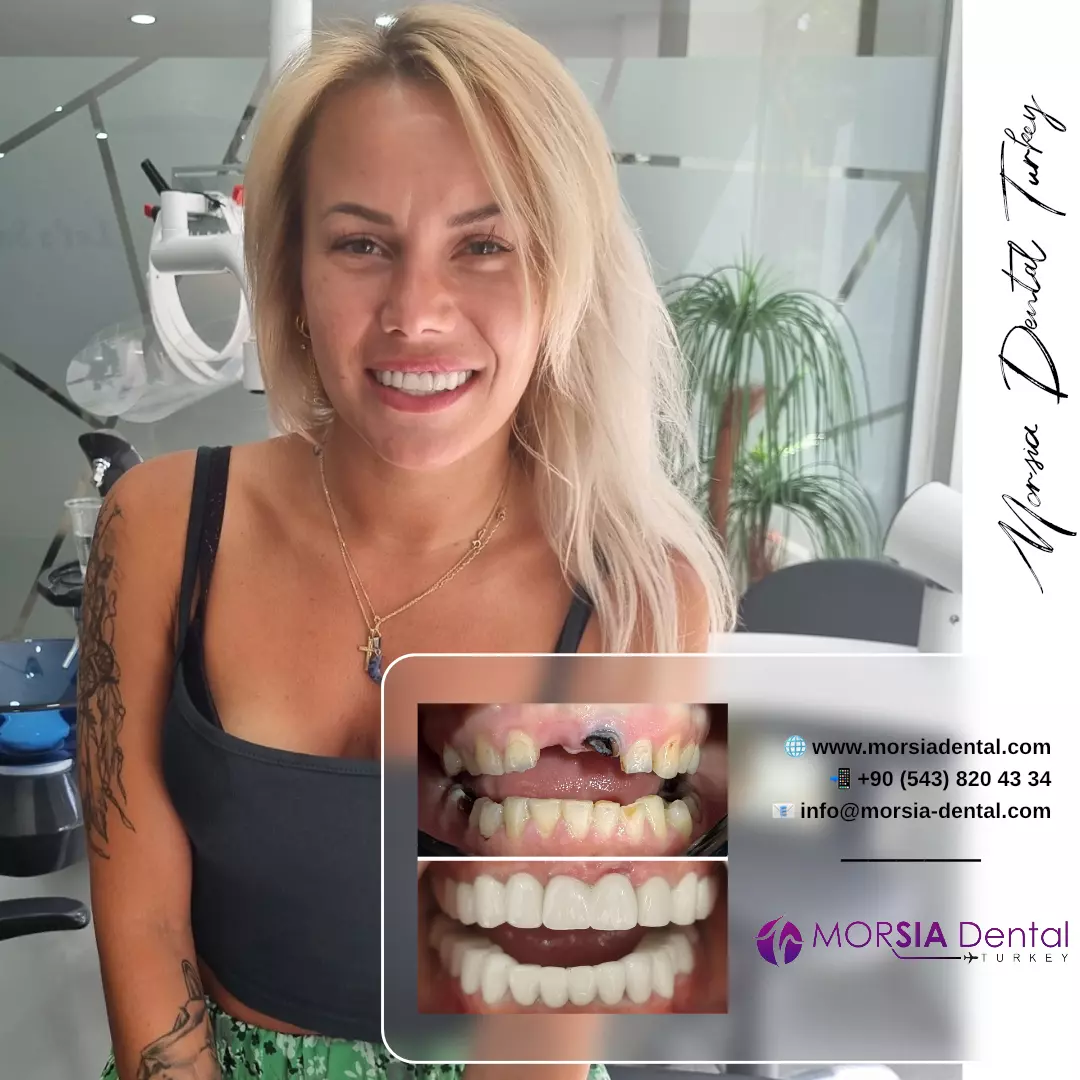

Ceux qui nous ont choisis

Ceux qui nous ont choisis

Découvrez les sourires transformés chez Morsia Dental.

Ceux qui nous ont choisis